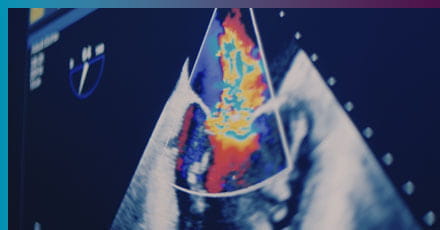

When it comes to your heart health, you can trust the experts at UPMC. We build multidisciplinary teams in every cardiovascular specialty, staffed with world-class caregivers. What do they all have in common? A commitment to providing exceptional, compassionate care. Learn what drives their work.